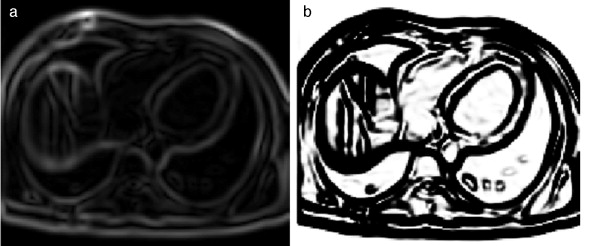

En la figura 7 se presenta la aplicación de dos rutinas del cálculo del gradiente en IRM cardiovascular. Obsérvese como los contornos son mejorados y se puede distinguir mejor el músculo miocardio y el ventrículo izquierdo. En la figura 7 .b se aplicó el operador Sobel en las direcciones x,y,z. En la figura 7 .c se presenta el resultado de aplicar el filtro itk::GradientMagnitudeRecursiveGaussianImageFilter[20]. Este filtro calcula la magnitud de la imagen gradiente por cada pixel o voxel. El proceso computacional consiste en primero suavizar la imagen a través de la convolución con una máscara Gaussiana y luego aplicar el operador diferencial.

Aplicación de las rutinas de módulo de una imagen gradiente. (a) IRM ...

Figura 7.

Aplicación de las rutinas de módulo de una imagen gradiente. (a) IRM cardiovascular original, solo se visualiza el corte axial número 33. (b) Aplicación del operador Sobel en x,y,z en la imagen (a). (c) Imagen módulo del gradiente de (a) empleando itk::GradientMagnitudeRecursiveGaussianImageFilter .

En la figura 8 se presenta la aplicación de la rutina del filtro sigmoid a partir de la imagen módulo gradiente mostrada en la figura 7 .c.

Reforzado de bordes empleando el filtro sigmoid. (a) Imagen módulo gradiente de ...

Figura 8.

Reforzado de bordes empleando el filtro sigmoid . (a) Imagen módulo gradiente de IRM cardiovascular l. (b) Imagen (a) con los bordes reforzados empleando en itk::SigmoidImageFilter .